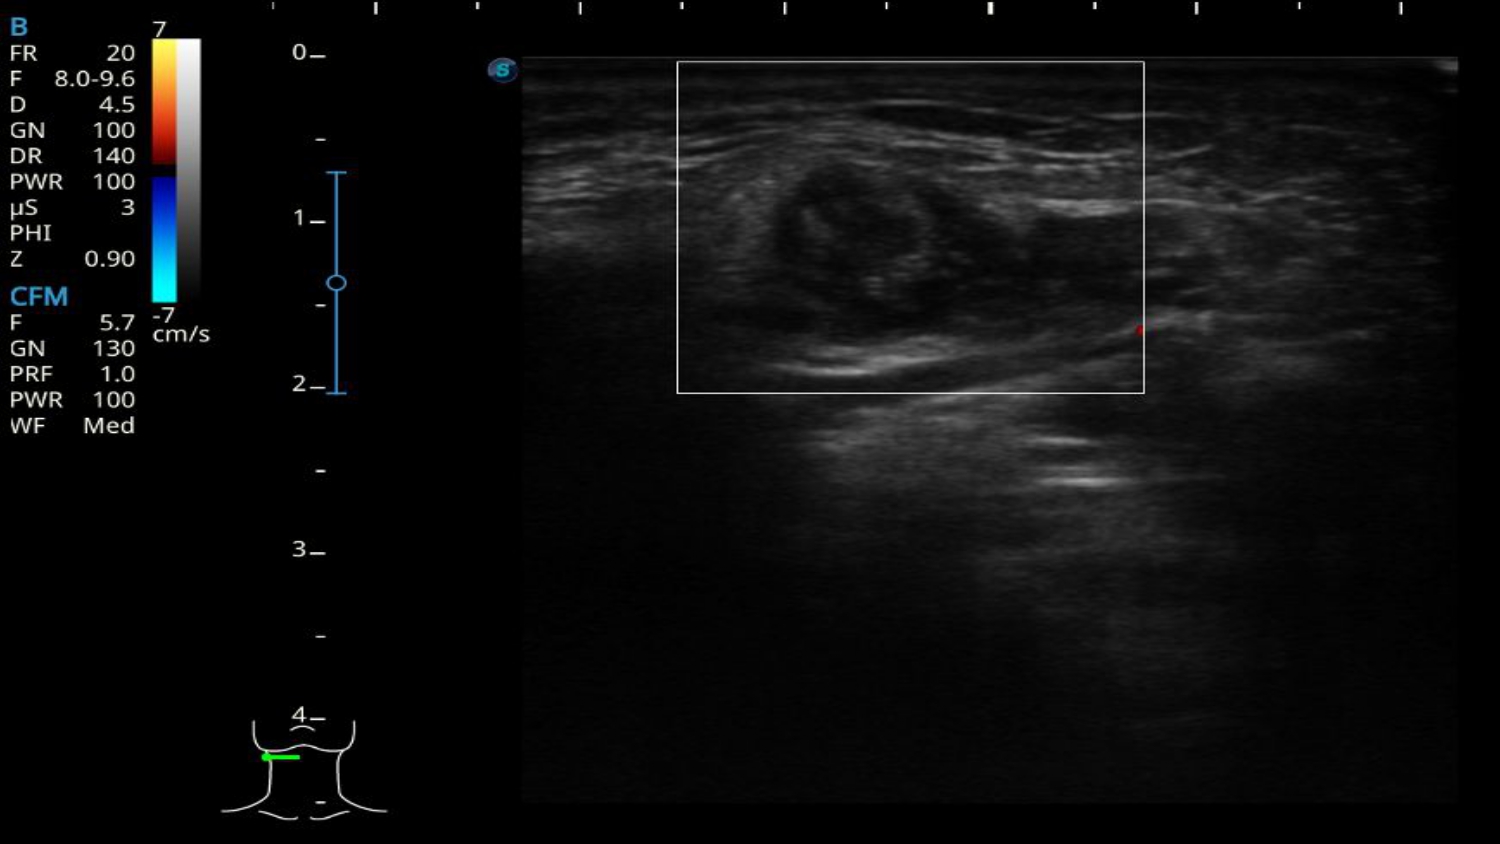

Hallazgos ecográficos

Se realiza ecografía que muestra imagen heterogénea redondeada encapsulada de 1 cm de diámetro, con discreta vascularización periférica, sin vascularización central a nivel de glándula submandibular derecha que podría ser compatible con adenoma pleomorfo. No se visualiza dicha imagen en región contralateral.